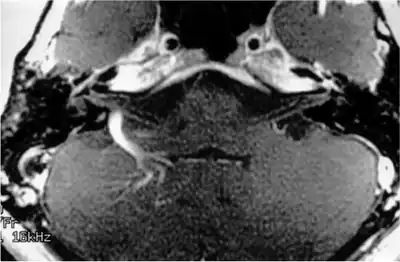

Magnetic resonance imaging

MRI scans can be used to identify gross structural causes of hearing loss. They are used for congenital hearing loss when changes to the shape of the inner ear or nerve of hearing may help diagnosis of the cause of the hearing loss. They are also useful in cases where a tumour is suspected or to determine the degree of damage in a hearing loss caused by bacterial infection or auto-immune disease. Scanning is of no value in age-related deafness.